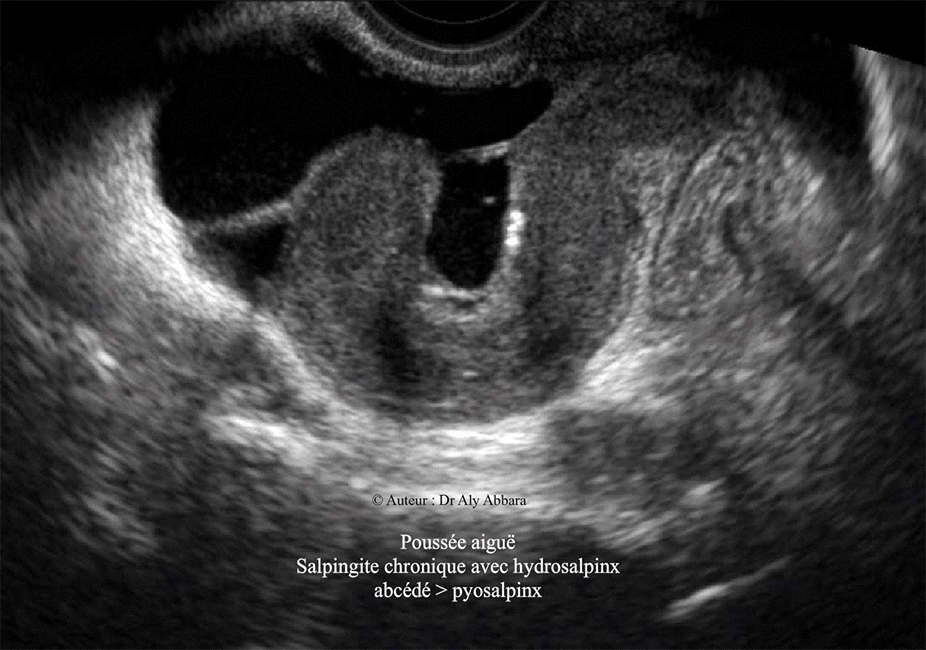

Salpingite chronique avec hydrosalpinx abcédé - Echographie

Image animée montrant l'aspect échographique d'une

salpingite chronique avec une poussée aiguë à l’origine de l'abcédation d'un hydrosalpinx

le transformant en pyosalpinx.